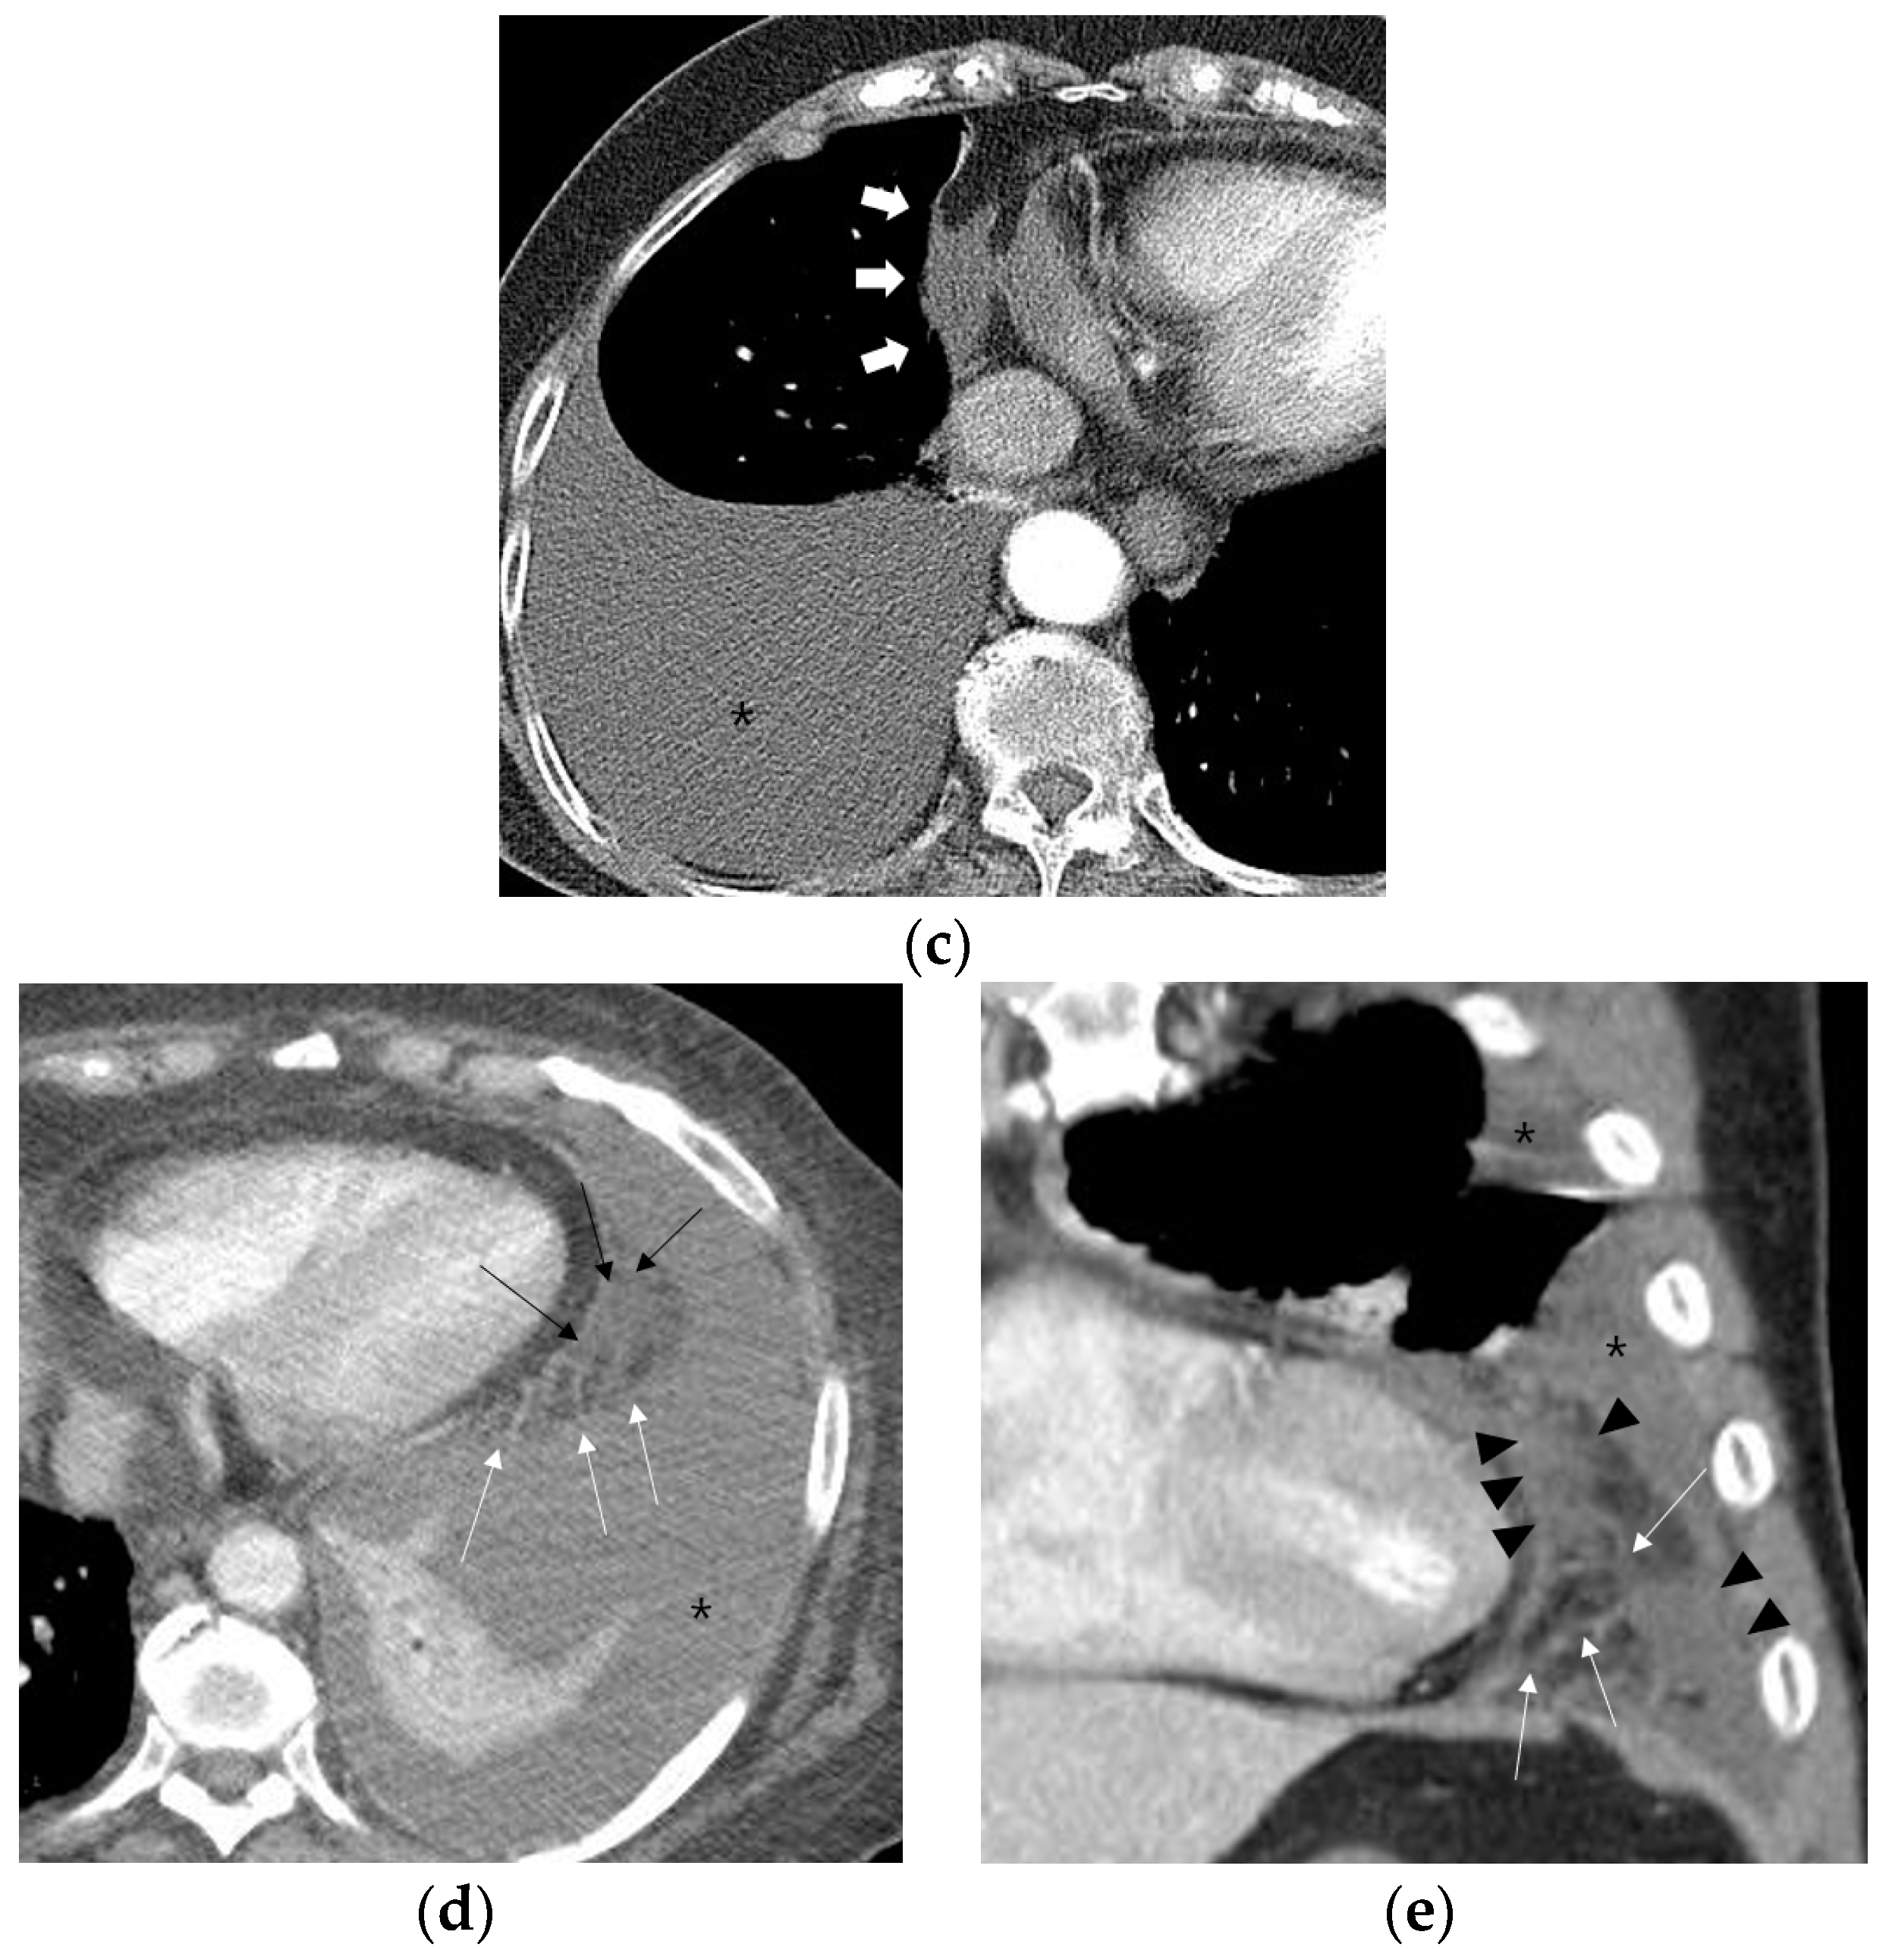

Figure 2.

Representative cases demonstrating normal appearance, fat stranding, fluid collection, and phlegmonous appearance in the ipsilateral paracardiac fat on chest computed tomography. (a) Normal appearance of paracardiac fat on a coronal CT image at the level of left ventricle. Note a lack of fat stranding or a fluid collection in the paracardiac fat of a patient with pleural tuberculosis (white arrows). (b) A case of right pleural tuberculosis (asterisks) in a 67-year-old female with fat stranding (black and white arrows) in the right paracardiac fat on an axial CT image at the level of the right ventricle. (c) A case of right pleural tuberculosis (asterisk) in a 77-year-old female demonstrating a fluid collection (white arrows) in the right paracardiac fat on an axial CT image at the level of the left ventricle. (d,e) Two cases of left pleural tuberculosis (asterisk) with a phlegmon-like appearance in left paracardiac fat in a 74-year-old female on axial CT image (d), and in a 58-year-old male on coronal CT (e) at the level of the left ventricle. Note multiple fat strands (white arrows) interspersed with multiple fluid collections (black arrows or black arrowheads) in the paracardiac fat ipsilateral to the left pleural effusion.